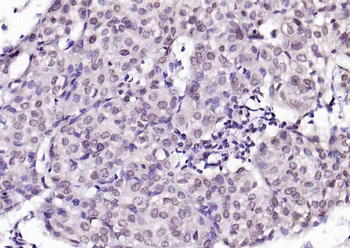

200 μl, 50 μl, 100 μlPhospho-CDKN1A/p21 (Thr57) Rabbit Polyclonal Antibody [orb6569]

FC, IF, IHC-Fr, IHC-P

Mouse, Rat

Human, Mouse, Rat

Rabbit

Polyclonal

Unconjugated

100 μl, 200 μl, 50 μl